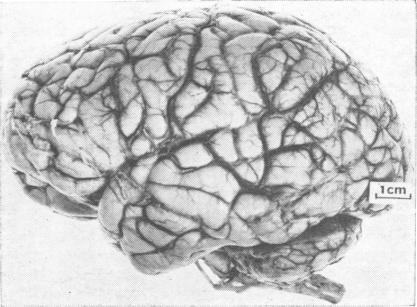

The clinical features in a new non-familial case of Cockayne's syndrome comprised the usual components: dwarfism with microcephaly, severe mental subnormality, progeria-like appearance of the face, pigmented retinopathy, and severe perceptive deafness. The patient also suffered from grand mal epilepsy and died in status epilepticus at the age of 22 years. The neuropathological findings were severe microencephaly, widespread calcifying vasopathy with some secondary degenerative changes in the contiguous tissue, and granular ependymitis.

侏儒症伴小头畸形、严重智力低下、面部早衰样外观、色素性视网膜病变和严重的感音神经性耳聋。该患者还患有大发作癫痫,并在22岁时死于癫痫持续状态。神经病理学检查结果为严重小头畸形、广泛的钙化性血管病,相邻组织有一些继发性退行性改变,以及颗粒性室管膜炎。